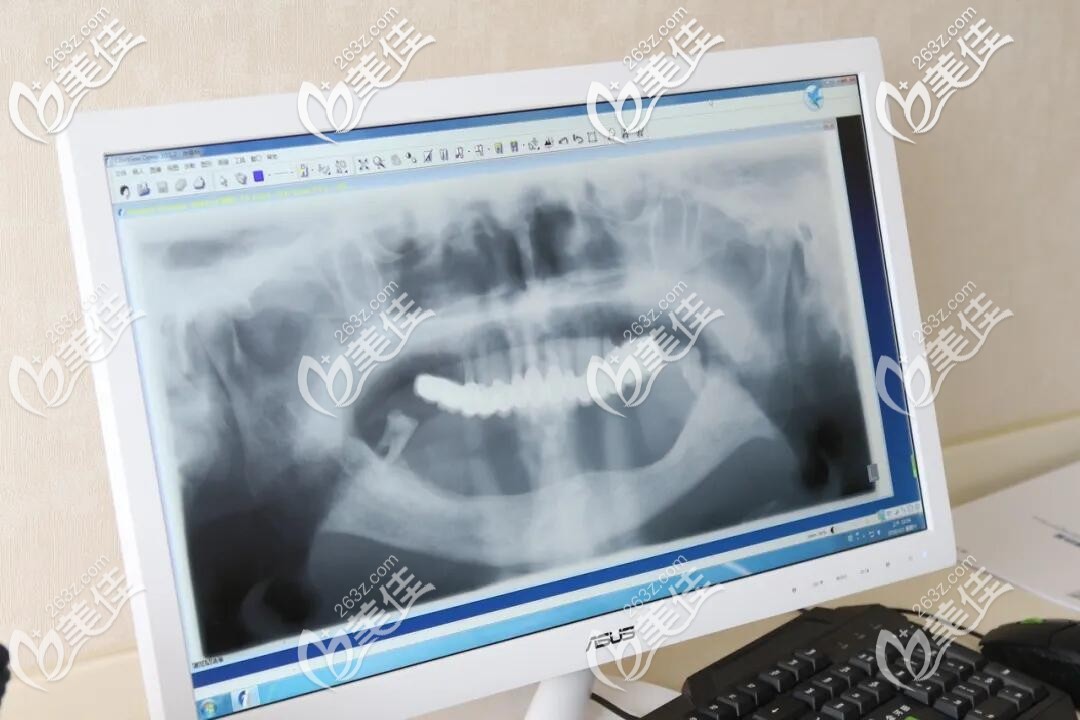

考慮到老爸的年齡和牙齒情況,需要做下半口種植,在進(jìn)行相應(yīng)的檢查后,特地找的是杭州美奧口腔院長(zhǎng)呈超院長(zhǎng)親自操刀,關(guān)院長(zhǎng)尤其擅長(zhǎng)高齡、口腔情況復(fù)雜的疑難病例,這讓我非常放心。